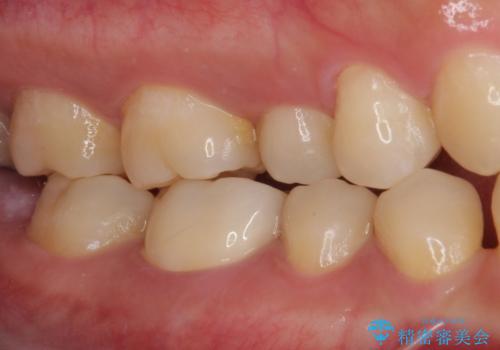

長年気にしていた銀歯を自然な色合いのセラミッククラウンに仕上げることができ、患者様には大変満足していただきました。